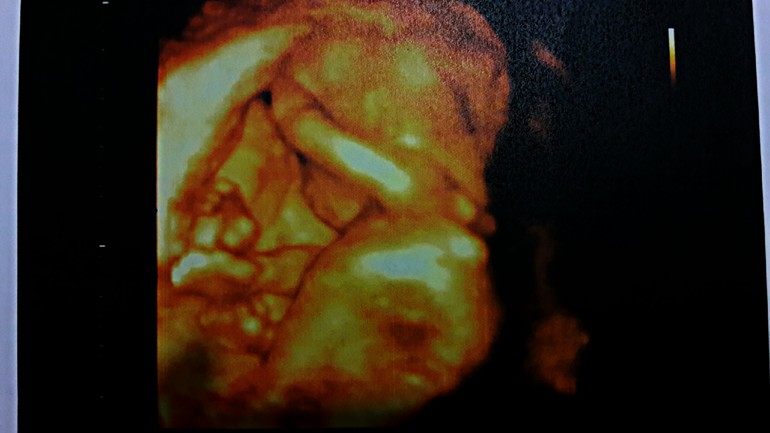

Доктор очень понравилась, все рассказала и показала. У нас оказалась девочка. Муж был уверен что у нас в животе сын. Расстроился конечно, но к вечеру привык к третьей дочери)) По месячным срок 16 и 1 неделя. По узи срок 17 и 6 недель. Крупненькие сказали. Со здоровьем и развитием все хорошо. Без отклонений. Рост 18 см, вес 200 гр. Размер ножки(ступни) 2.5 см. И фото малышки на память и самого узи: